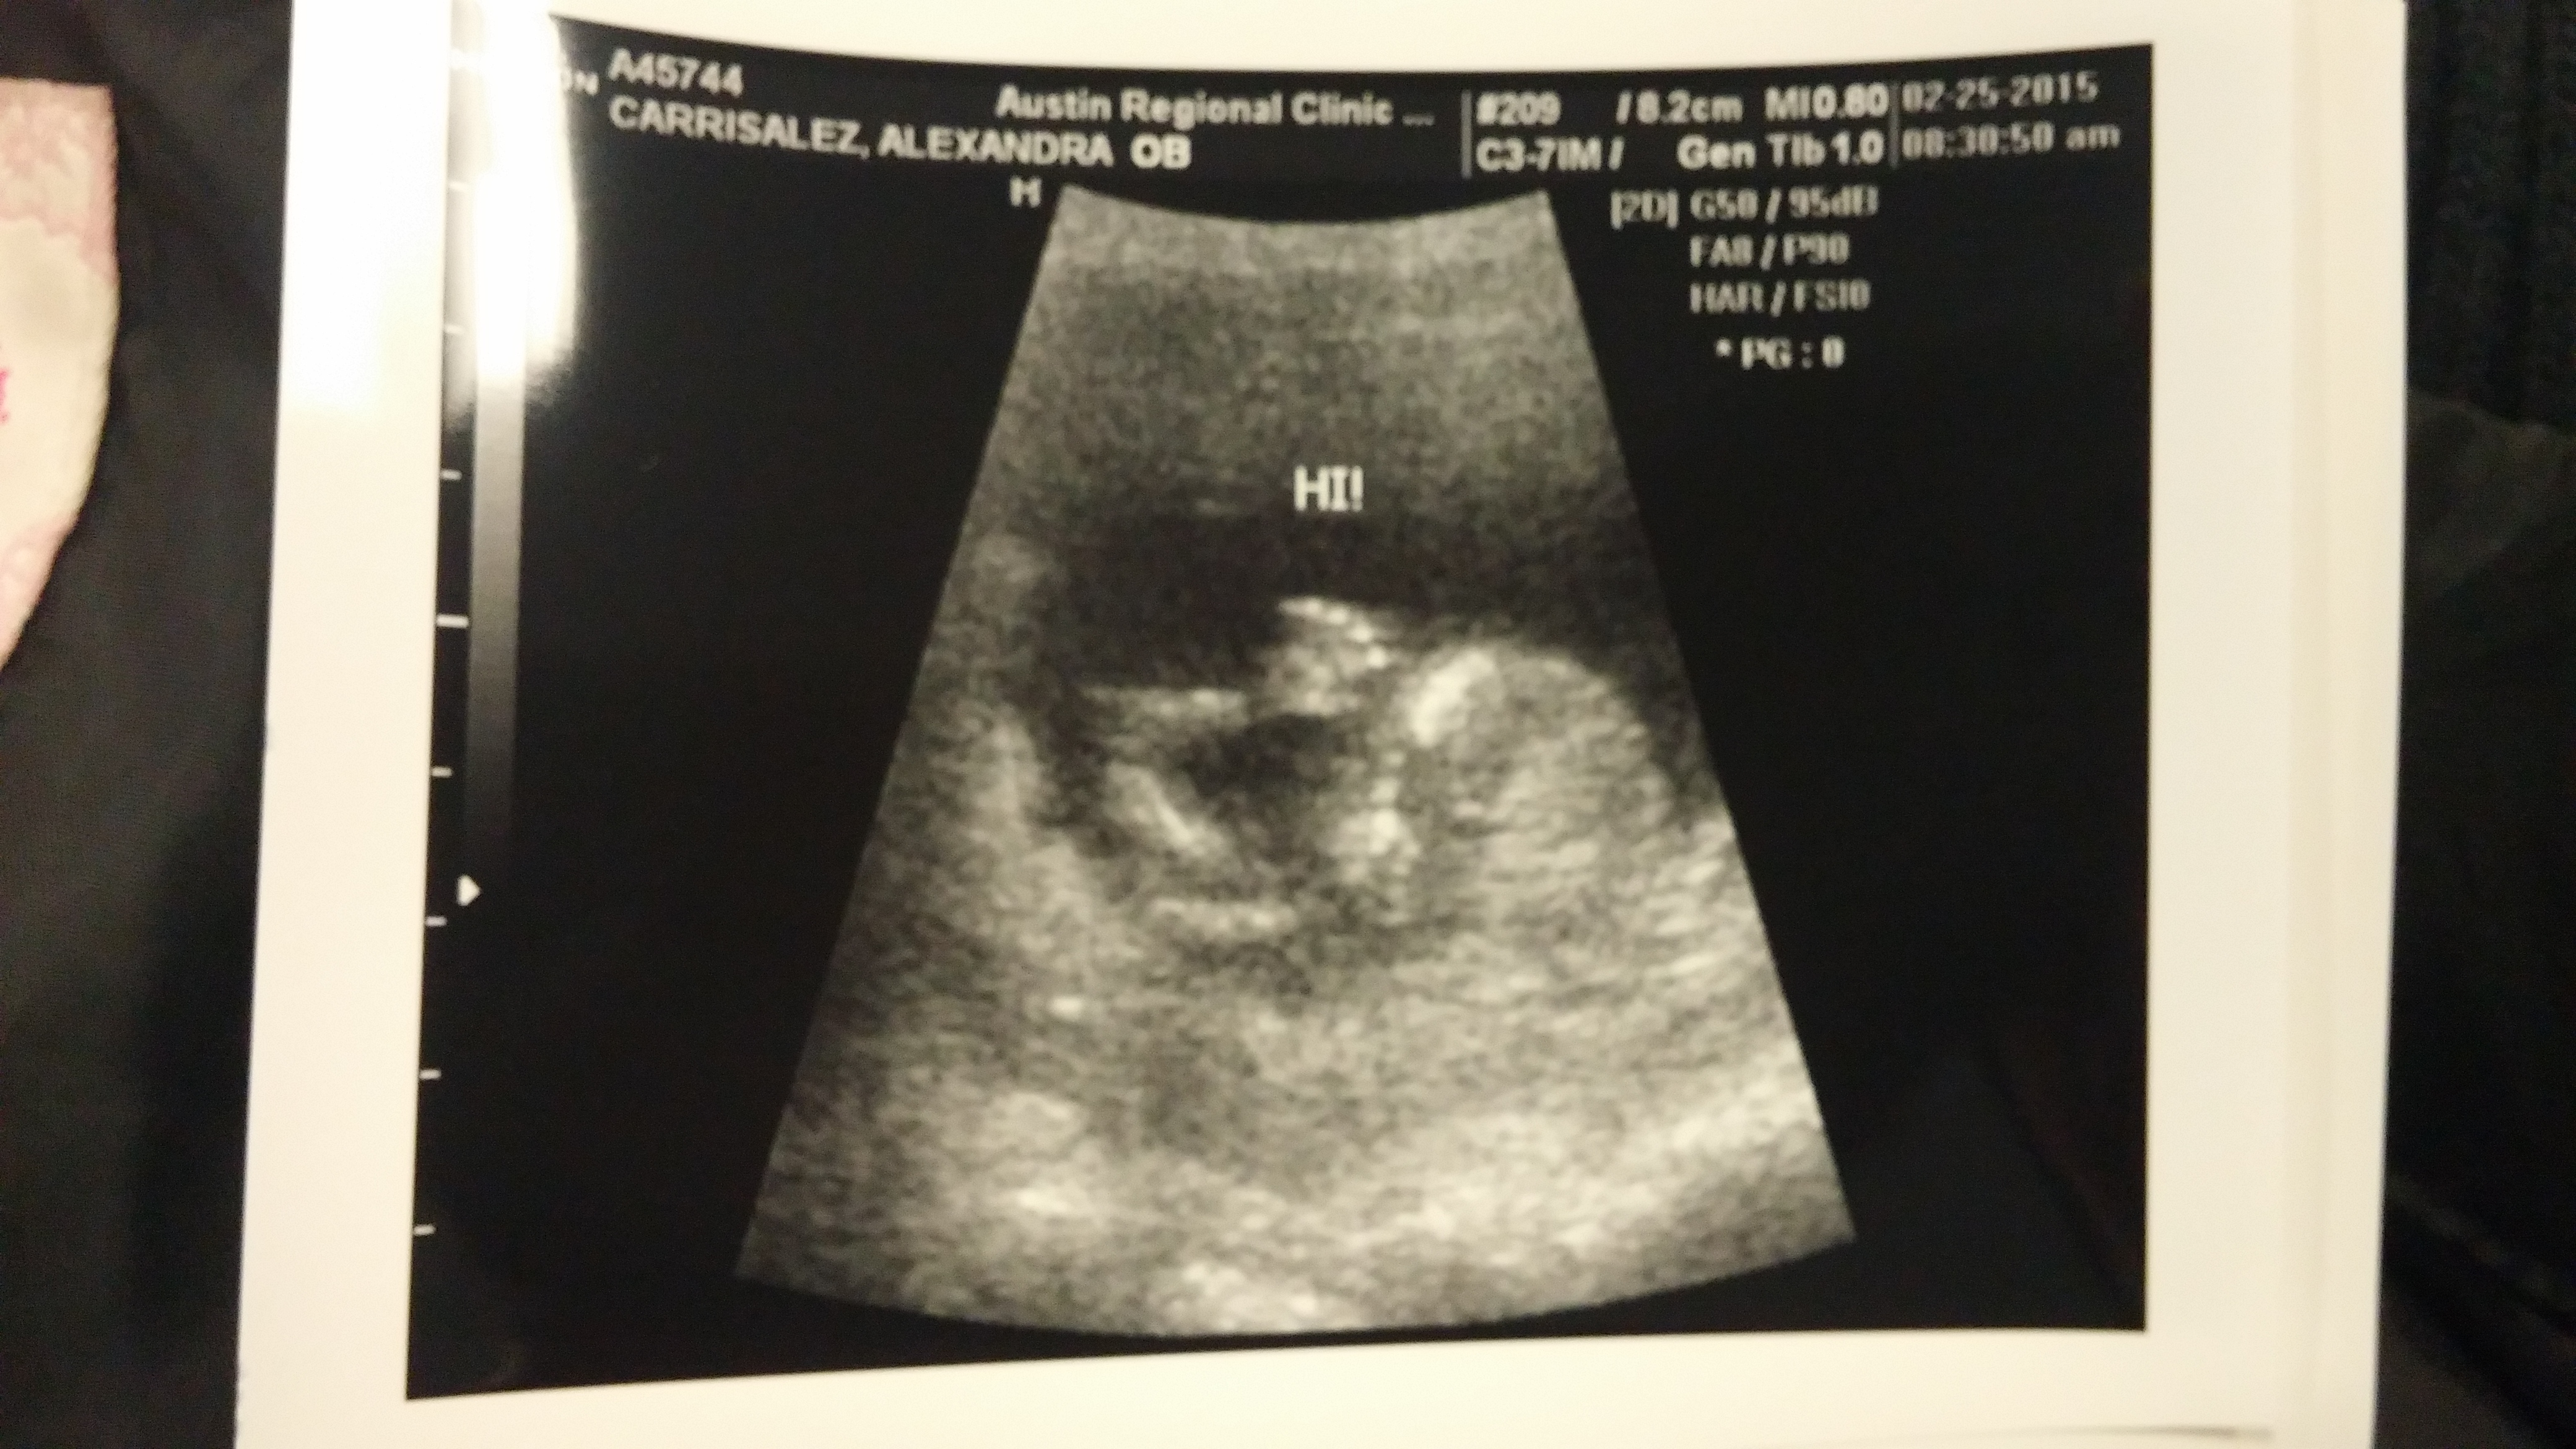

I got one at 7w and then today at 12w.(surprise extra u/s since the doppler couldn't pick up the heartrate!) Our little baby has grown a lot in 5 weeks!